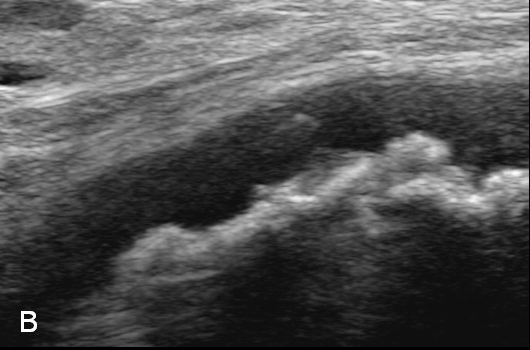

Figure 3

Duplex Sonographic (DS) images from three distinct arterial segments. Arterial segment (A) is classified as “vasculitis”, with homogenous, hypoechoic wall broadening, segment (B) as “arteriosclerosis”, with eccentric, irregular plaques and acoustic shadowing, and segment (C) as “normal”, showing a thin homogenous intima/media layer.